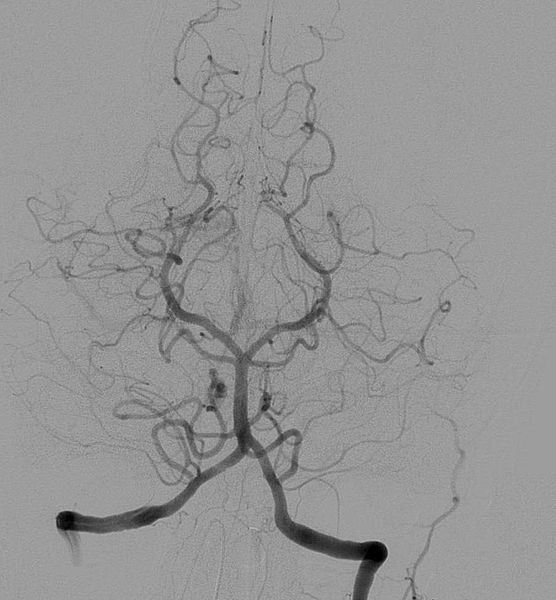

血管摄影,或称动脉摄影、血管造影,是一种医学影像技术,用x光照射人体内部,观察血管分布的情形,包括动脉、静脉或心房室。 葡萄牙籍医师兼神经学家Egas Moniz(1949年诺贝尔奖的得主)在1927年发展出利用显影剂执行脑部的血管摄影,诊断出一些神经疾病,例如肿瘤以及动静脉畸形,他被认为是这个领域的先趋者之一。随着Seldinger技术于1953年的发明,不再需要将锐利的导入装置留在血管腔内,使得它更加地安全。

由于血液和周边的组织有相同的阻射率(Radiodensity),需要加入会吸收x光的显影剂,使得血管可以轻易地被看见,在心血管的结构中,有显影剂的话,在血管摄影的影像中看起来是一个通道状的阴影,血管组织和心房室本身几乎是看不见的。

使用脑血管造影术显示的基底动脉和大后脑动脉的端平面 | |